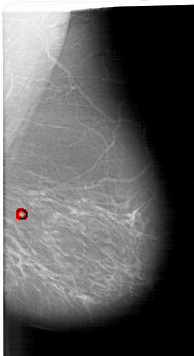

A_1349_1.LEFT_CC

LEFT_CC LINES 6751 PIXELS_PER_LINE 3526 BITS_PER_PIXEL 12 RESOLUTION 43.5 NON_OVERLAY

FILE: A_1349_1.RIGHT_CC.OVERLAY

TOTAL_ABNORMALITIES 1

ABNORMALITY 1

LESION_TYPE CALCIFICATION TYPE PLEOMORPHIC DISTRIBUTION SEGMENTAL

ASSESSMENT 4

SUBTLETY 4

PATHOLOGY BENIGN

TOTAL_OUTLINES 1

BOUNDARY